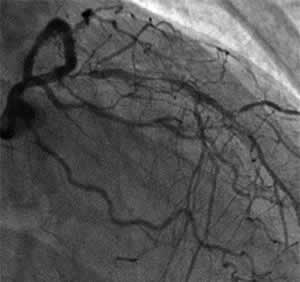

| Diagnosis: OMI (A), AP, SVD

Present Illness: '97.9 AMI (A) '00.11~ AP '00.12.13 Stenting for LCX '01.1.24 Stenting for #6 PCI for #7 CTO (unsuccess) '01.5.9 POBA+stenting for #6 distal |

| Coronary Risk Factor: DM |

| Final CAG Findings:'01.9.5 LVG: asynergy (A), EF: 71% CAG: #6 90% (ISR) #7 CTO (collateral from RCA) |